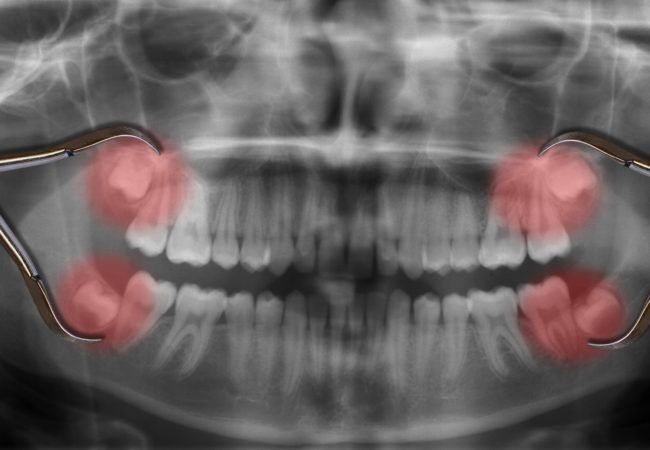

Răng khôn hay còn gọi là răng số 8. Đây là răng mọc cuối cùng trên cung hàm, thông thường mọc trong giai đoạn từ 17 – 30 tuổi. Mỗi người có tối đa 4 răng khôn mọc ở 4 góc hàm. Nhổ răng khôn mọc lệch giá bao nhiêu tiền luôn được nhiều người quan tâm bởi mỗi nha khoa có một mức giá khác nhau. Vậy yếu tố nào quyết định đến giá nhổ răng khôn? Cùng DDS tìm hiểu qua bài viết dưới đây:

Trên thực tế, việc nhổ răng khôn hàm trên được nhiều người đánh giá dễ dàng hơn việc nhổ răng khôn hàm dưới. Điều này được giải thích dựa vào cấu tạo chung của khuôn hàm, thường thì kích thước hàm dưới nhỏ hơn hàm trên, răng khôn mọc ở dưới sẽ có xu hướng mọc lệch, mọc ngầm nhiều hơn.

Hầu hết răng khôn mọc lệch ở hàm dưới đều có phần chân răng bị biến dạng, cong, vênh nên việc nhổ bỏ sẽ khó khăn hơn, có trường hợp phải cắt chân răng ra làm nhiều phần mới lấy hết chân răng ra được. Đây là lý do mà việc nhổ răng khôn ở hàm dưới sẽ phức tạp hơn và mất nhiều thời gian hơn.